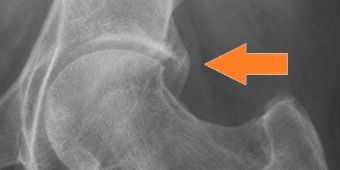

pinzer-impingement

Großer Knochensporn (Pfeil) am Pfannendach der einklemmt und somit entfernt werden muss. © Asklepios

Impingement- oder Einklemmungssymptome am Hüftgelenk sind nicht seltene Ursachen von Hüftgelenkbeschwerden. Allerdings wurde das Hüftimpingement erst im Jahr 2003-2004 als eine der wichtigsten Ursachen für eine sekundäre Hüftarthrose identifiziert und die Hüftarthroskopie als kausale Behandlung etabliert.

Beim Hüftimpingement können ein stark vorstehender knöcherner Pfannenrand (Pincer- oder Beißzangen-Impingement; Bild) oder ein inhomogener knöcherner Übergang des Hüftkopfes in den Schenkelhals (sog. CAM- oder Nockenwellen-Impingement) bei Bewegungen im Hüftgelenk Beschwerden verursachen, die schon im Kindes- oder Jugendalter – ggf. durch Vorerkrankungen wie ein Hüftkopfabrutsch (Epiphyseolyse) oder ein Hüftkopfzerfall (Morbus Perthes) – beginnen.